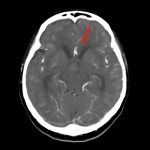

断層撮影